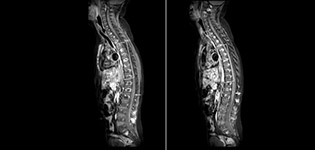

Fat saturation is historically challenging at the ends of fields of view, especially in total spine imaging and in difficult patient anatomy such as the lower regions of the neck. “Due to the unique fat suppression capabilities of mDIXON, however, these challenges no long apply,” says Dr. Miller. “We routinely obtain homogeneous fat suppression under virtually all conditions. It has also led to some efficiencies by not having to repeat sequences because of that technical failure.”

“mDIXON TSE is most useful in patients with lesions or abnormalities in the soft tissues such as the face and neck, and for patients with contrast enhancing abnormalities that are mostly visible with fat suppression,” says Dr. Miller. “All our spine imaging now routinely contains mDIXON water-only T2 images, and this allows us to identify pathology that may be obscured by non-fat suppressed imaging such as injuries of the bone. And it’s not necessary to obtain additional standard TSE T2 images because the in-phase mDIXON images are equivalent to standard TSE T2 images.”

“mDIXON TSE has increased our diagnostic confidence in ruling in or ruling out abnormalities in which fat suppression is critical to diagnosis, such as metastatic disease or osseous abnormalities.”

Miller JH, Pokorney A, Naidu P, Eggers H, Shar M, Perkins T. Improved Fat Suppression and Field Homogeneity of mDixon TSE Total Spine Imaging compared to SPIR Fat Saturation for Post-Contrast T1-weighted Imaging. Proceedings of the Joint Annual Meeting of the ISMRM-ESMRB. Milan, Italy: International Society for Magnetic Resonance in Medicine, 2014.